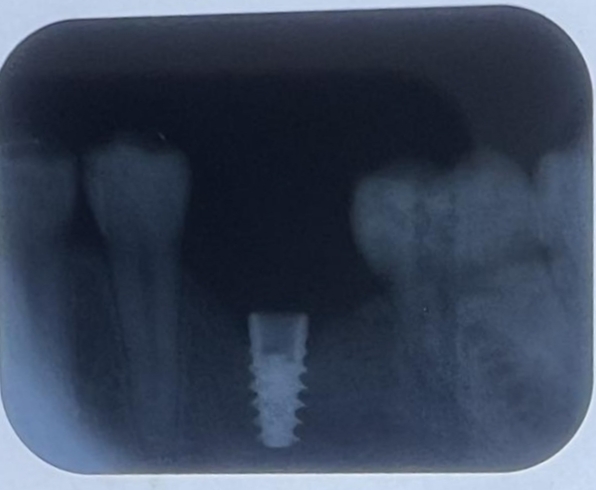

Some of the most rookie mistakes can be a fractured screw of an abudment. It’s really annoying but that involves in some cases. Let’s say you made a perfect All on X case with perfect prothesis all good 👍🏻 till now.…

• Thank you for sharing Mohamed! For those of us who might not understand the first picture. Can you tell us what that is? Is it an abutment that is cold welded to the implant?